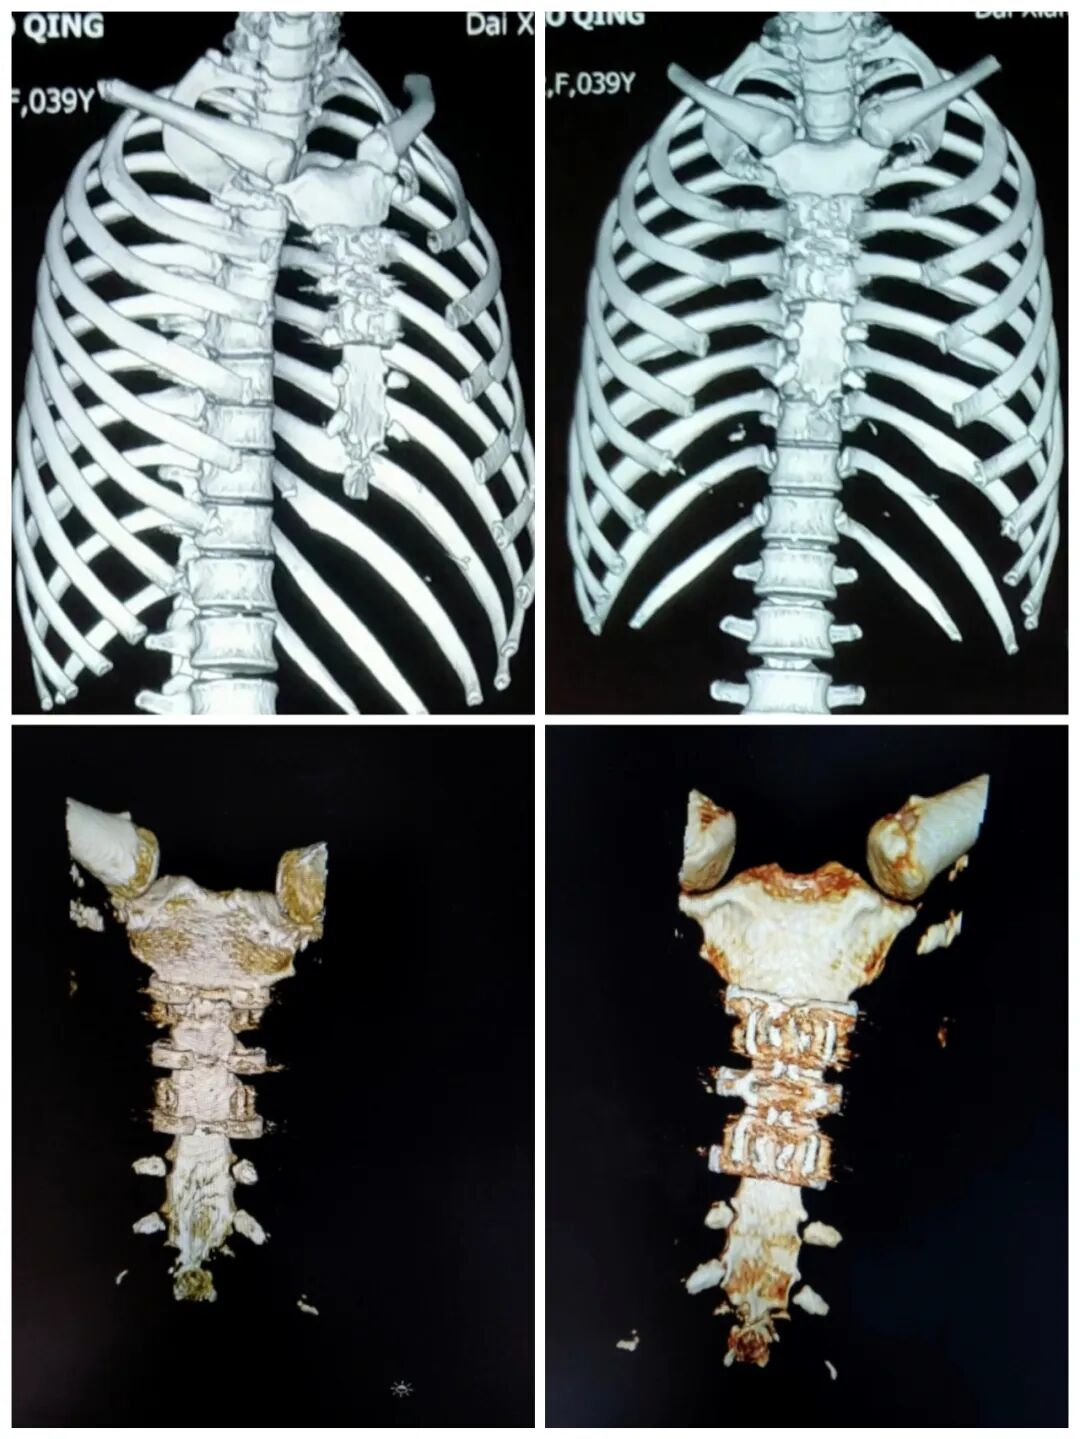

术后影像

经双方医疗团队密切协作,成功完成手术,患者术后恢复良好。